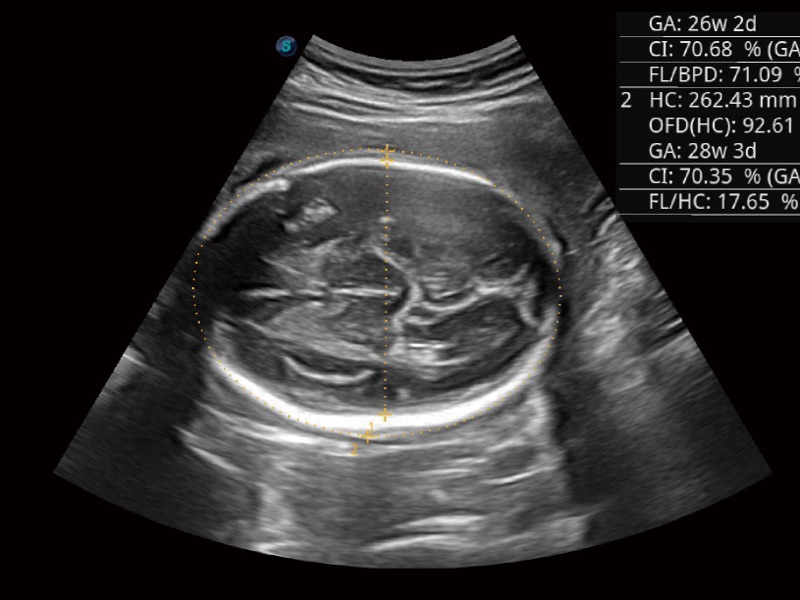

妇产科应用

宽频带及多频段变频结合16877太阳集团频率复合技术,使得每一支探头可以很好地给临床带来穿透力与分辨率的完美结合,图像真实,提供临床诊断准确性。

微米成像技术大大提高了器官和病变的可见性。高清对比度分辨率将抑制斑点噪声,同时保持真实的组织结构。